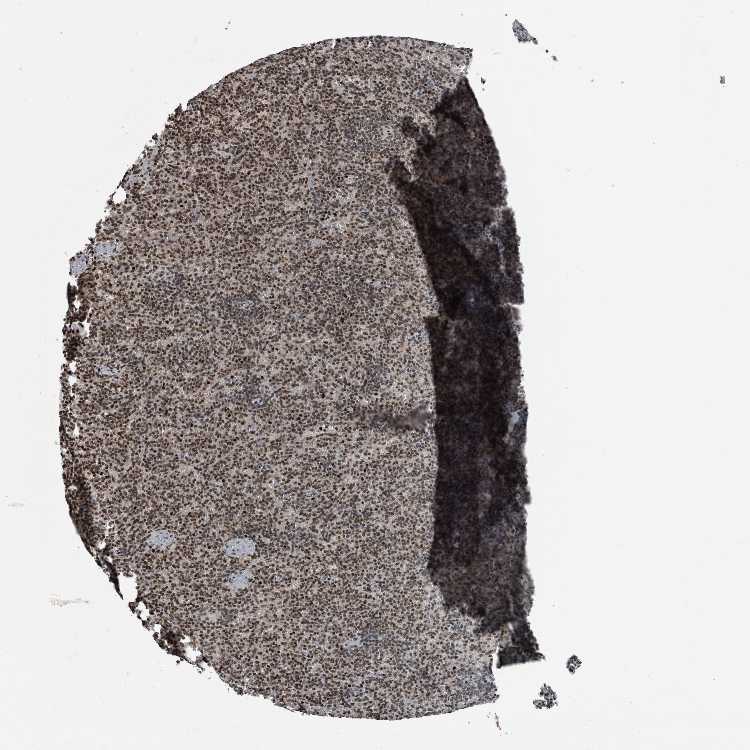

Antibody HPA027009

Cells in red pulp Medium

Cells in white pulp Low